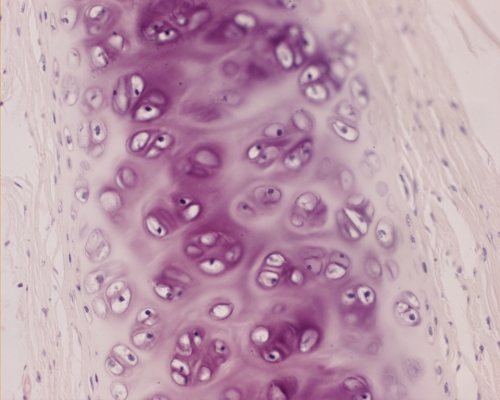

Differences in the connective tissues of bone, skin and cartilage are in part explained by differences in the content of specific components. For example,

Differences among the connective tissues also depend on the three-dimensional organization of the molecular components. The type I collagen fibrils in tendon are packed into thick, parallel bundles of fibres, whereas type I collagen fibrils in skin are randomly oriented. In cortical bone, helical arrays of type I collagen fibrils are deposited around haversian canals. |